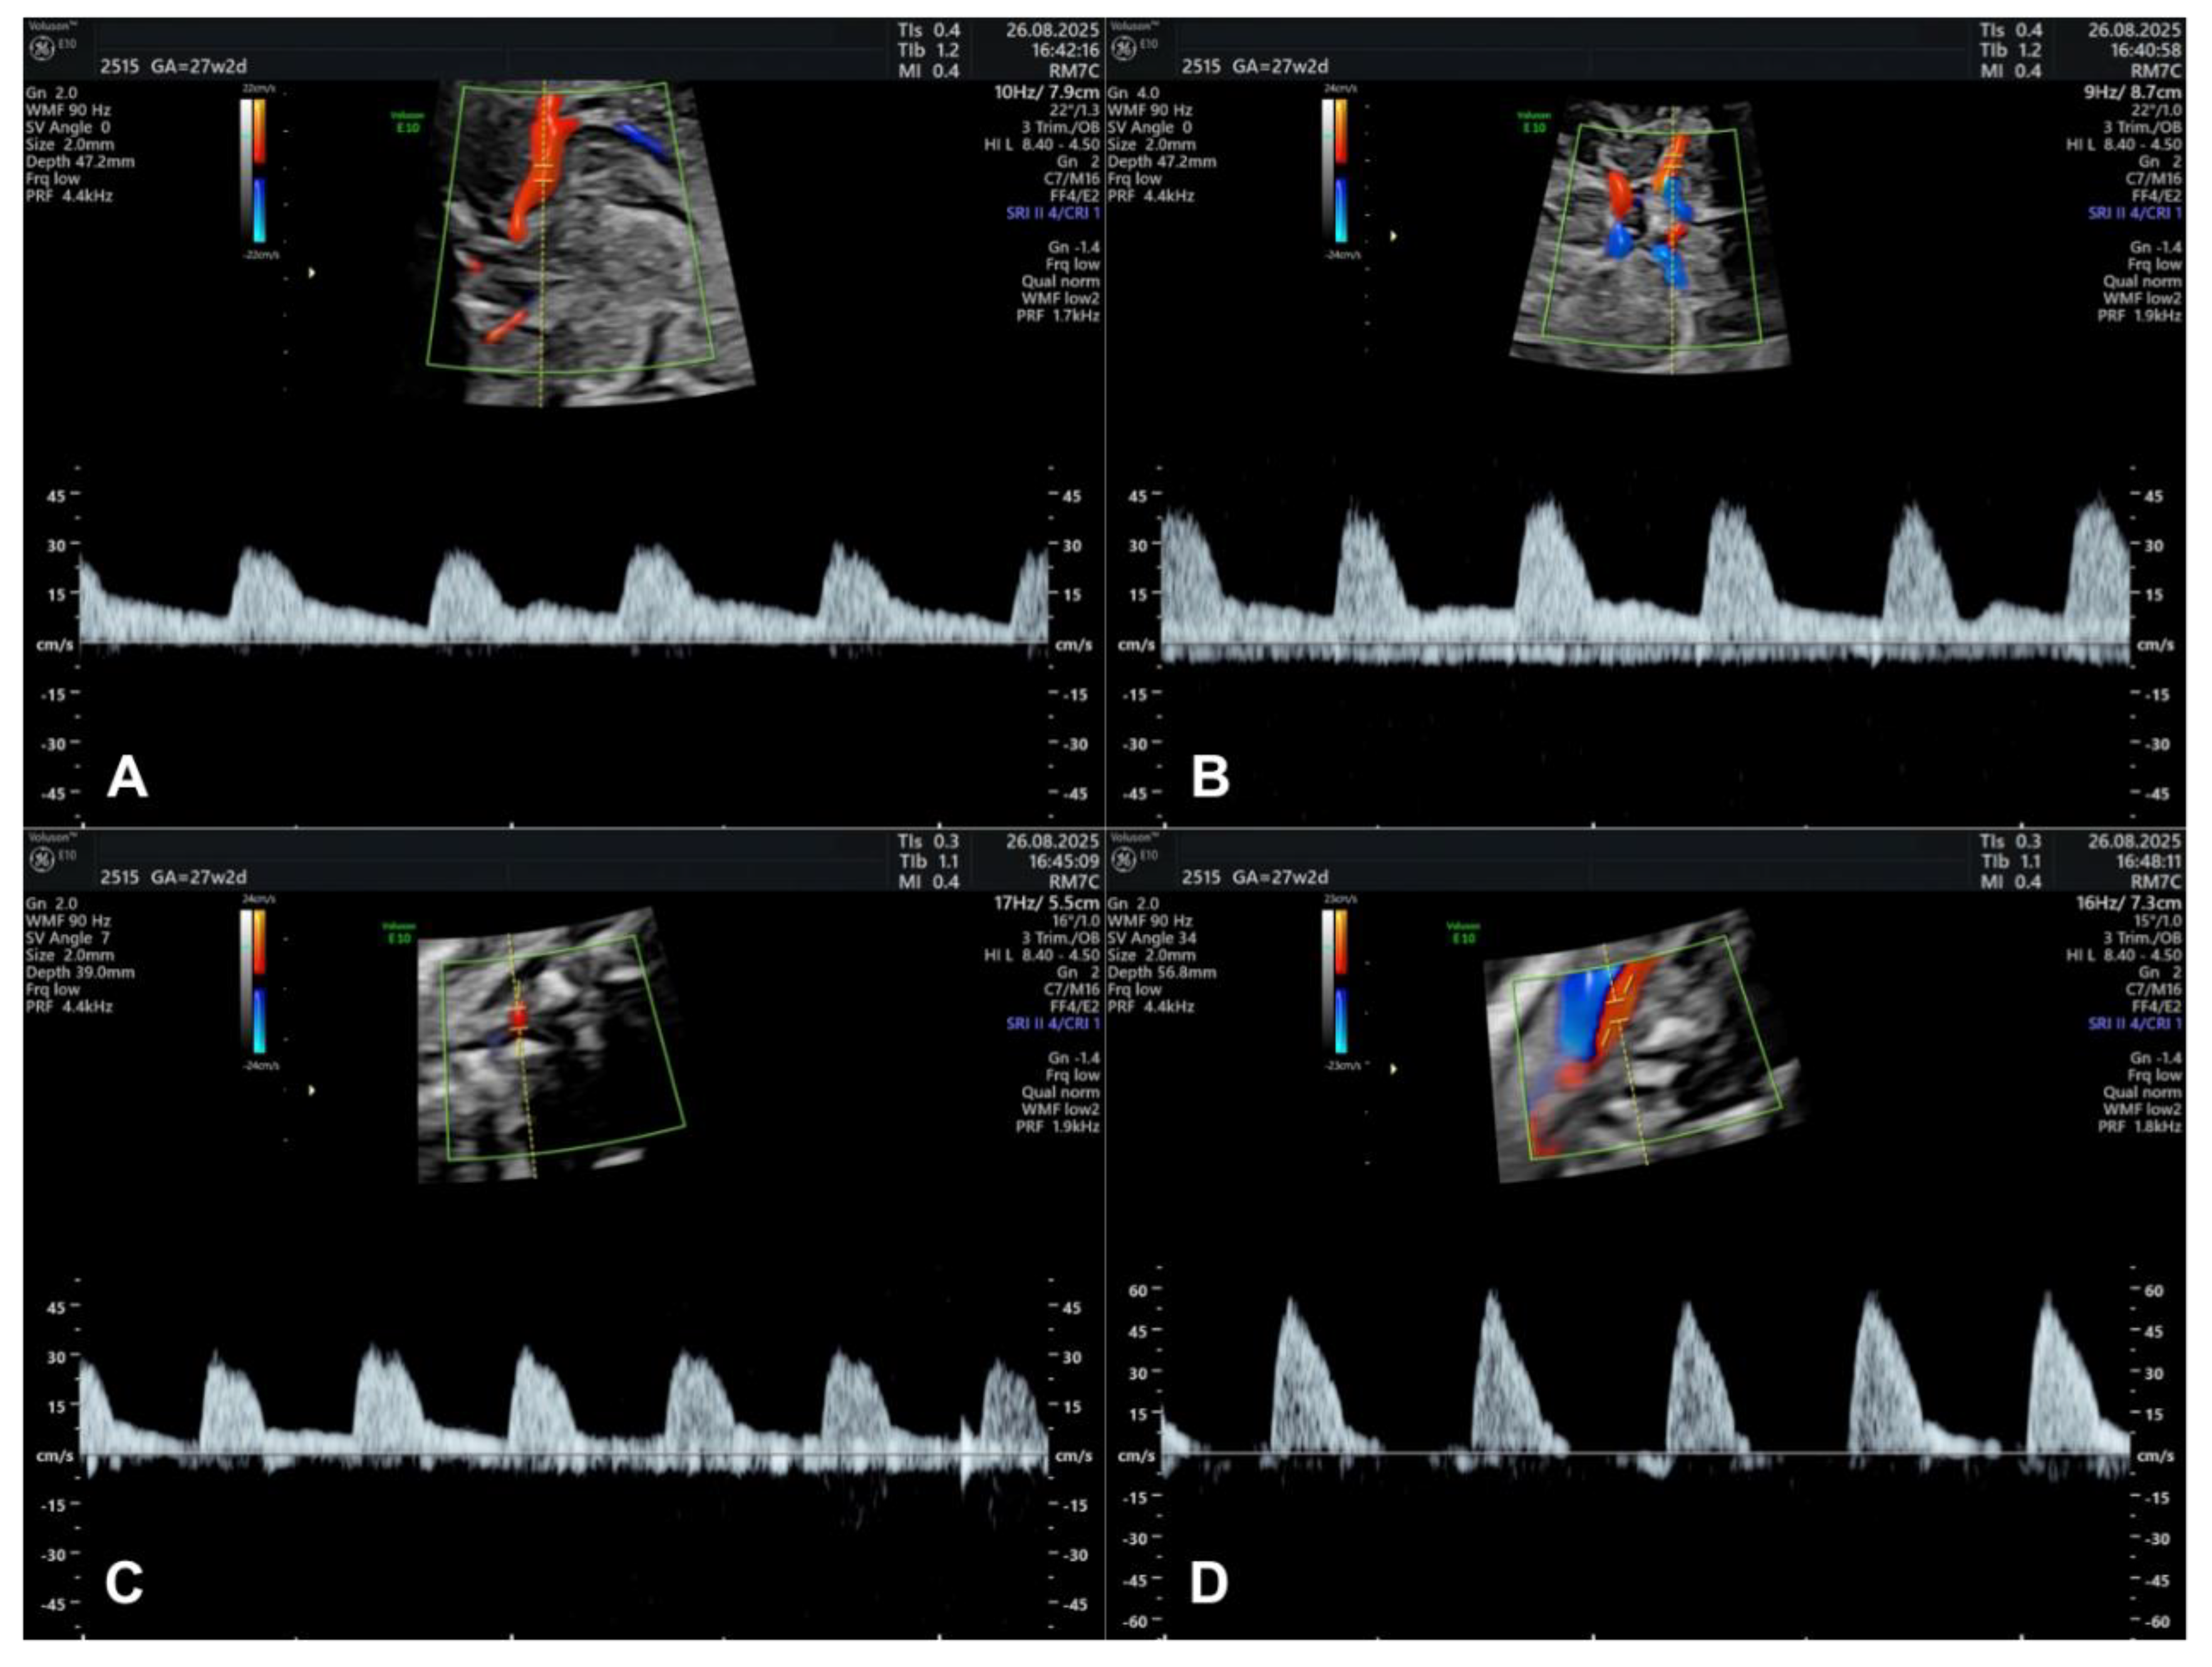

3.7. Doppler Studies of Foetal Cerebral Blood Flow